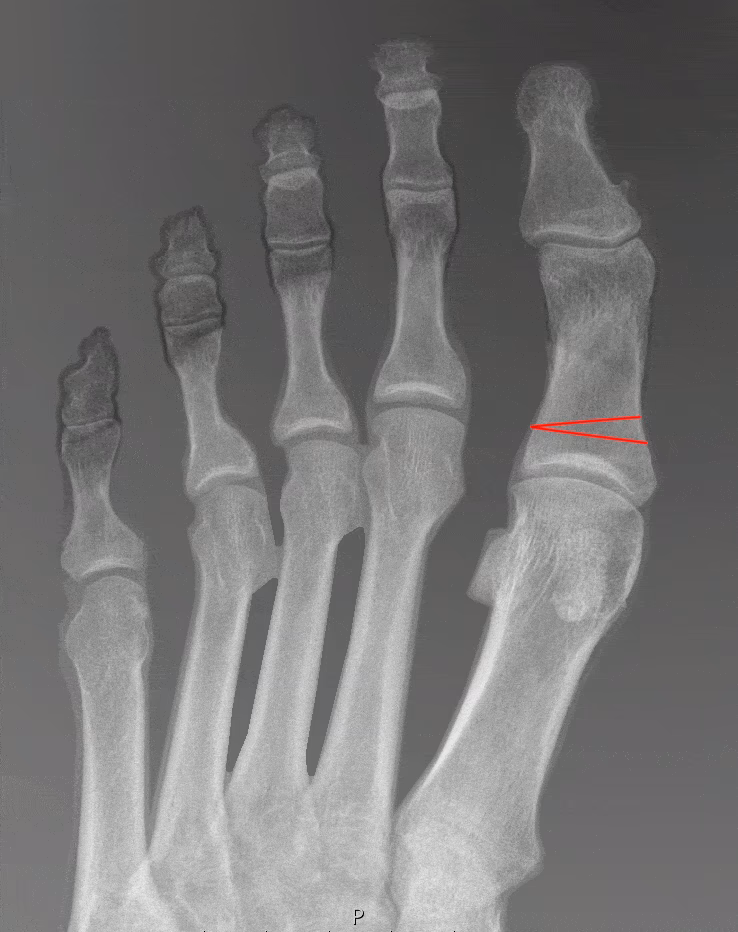

Røntgenbilleder taget, mens du står op, er essentielle. De giver kirurgen et præcist billede af knoglestrukturen og de vinkler, der skal korrigeres. Følgende måles typisk:

- Hallux Interphalangeus Vinkel (HIA): Vinklen inde i selve storetåen, som er den primære vinkel, en Akin osteotomi korrigerer.